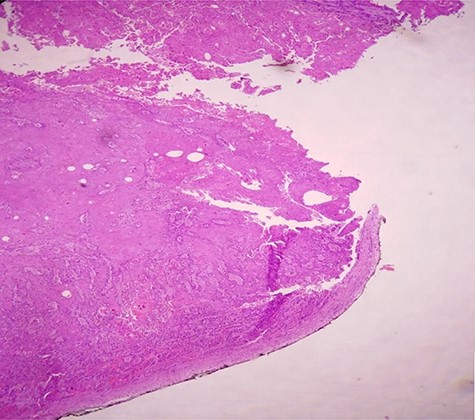

Postoperative course was marked by an aggravation of the septic shock, multiorgan failure, and death of the patient at Day 2 after surgery. Pathological examination concluded a pure SCC that massively invades the bladder muscle and perivesical fat (Figs 4–6).

H & E staining viewed under x40 with Olympus CX23 showing a well differentiated SCC (Presence of keratin pearls and intercellular bridges).